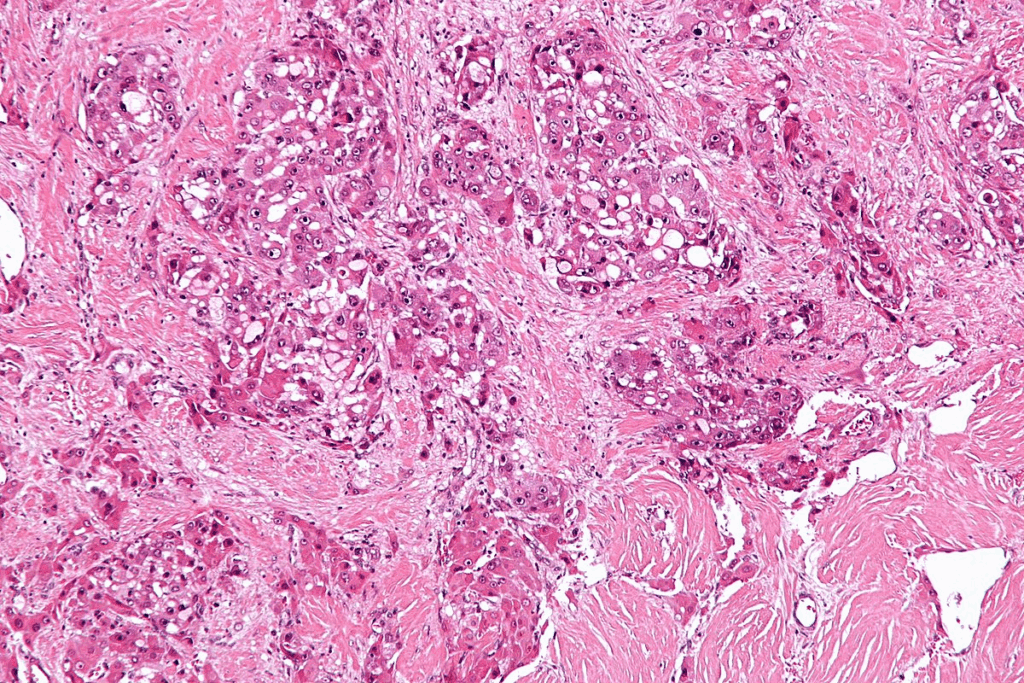

Histological Features

The features of CIS are key for its diagnosis. CIS shows marked nuclear enlargement, hyperchromasia, and loss of cellular polarity in the urothelium. These abnormal cells stay in the epithelial layer and haven’t invaded deeper tissues. The urothelium looks disordered or chaotic, with cells showing a lot of pleomorphism.

Looking at the cells under a microscope is vital to tell CIS apart from other bladder issues. The diagnosis of CIS relies on these specific cell features.